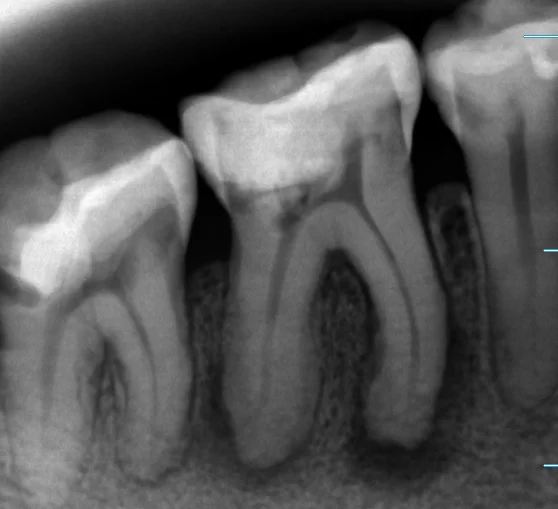

歯質を温存しながら左上の臼歯3本をダイレクトボンディングで修復

東京都内からお越しの30代女性(歯科医師)の患者さんです。経過観察していた左上5番 近心のむし歯が象牙質の半ば(1/2程度)まで進行したため、左上4・5・6番の3本を同日にダイレクトボンディングで修復した症例です。健康な歯質を最大限温存することを優先し、ラバーダム防湿下で精密に接着処理を行いました。